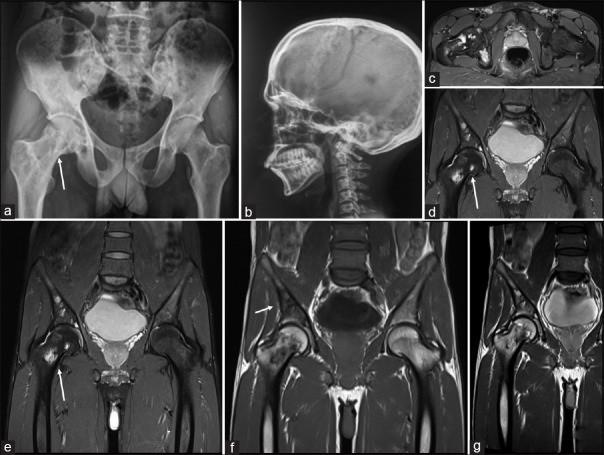

| Figure 2:A 28-year-old male presenting with pain: (a) plain radiographs of the pelvis (white arrow) and (b) plain Radiograph Skull lateral shows no calvarial lesions but (c) magnetic resonance imaging axial fat suppressed ill-defined lytic lesions in the trochanter (d and e) coronal fat suppressed magnetic resonance images shows multiple hyperintense areas in the femoral head, trochanter (white arrows) (f) magnetic resonance imaging coronal T1 and (g) magnetic resonance imaging coronal T2 show lesions also in bilateral sacral alae, sacral vertebrae and bilateral iliac bones